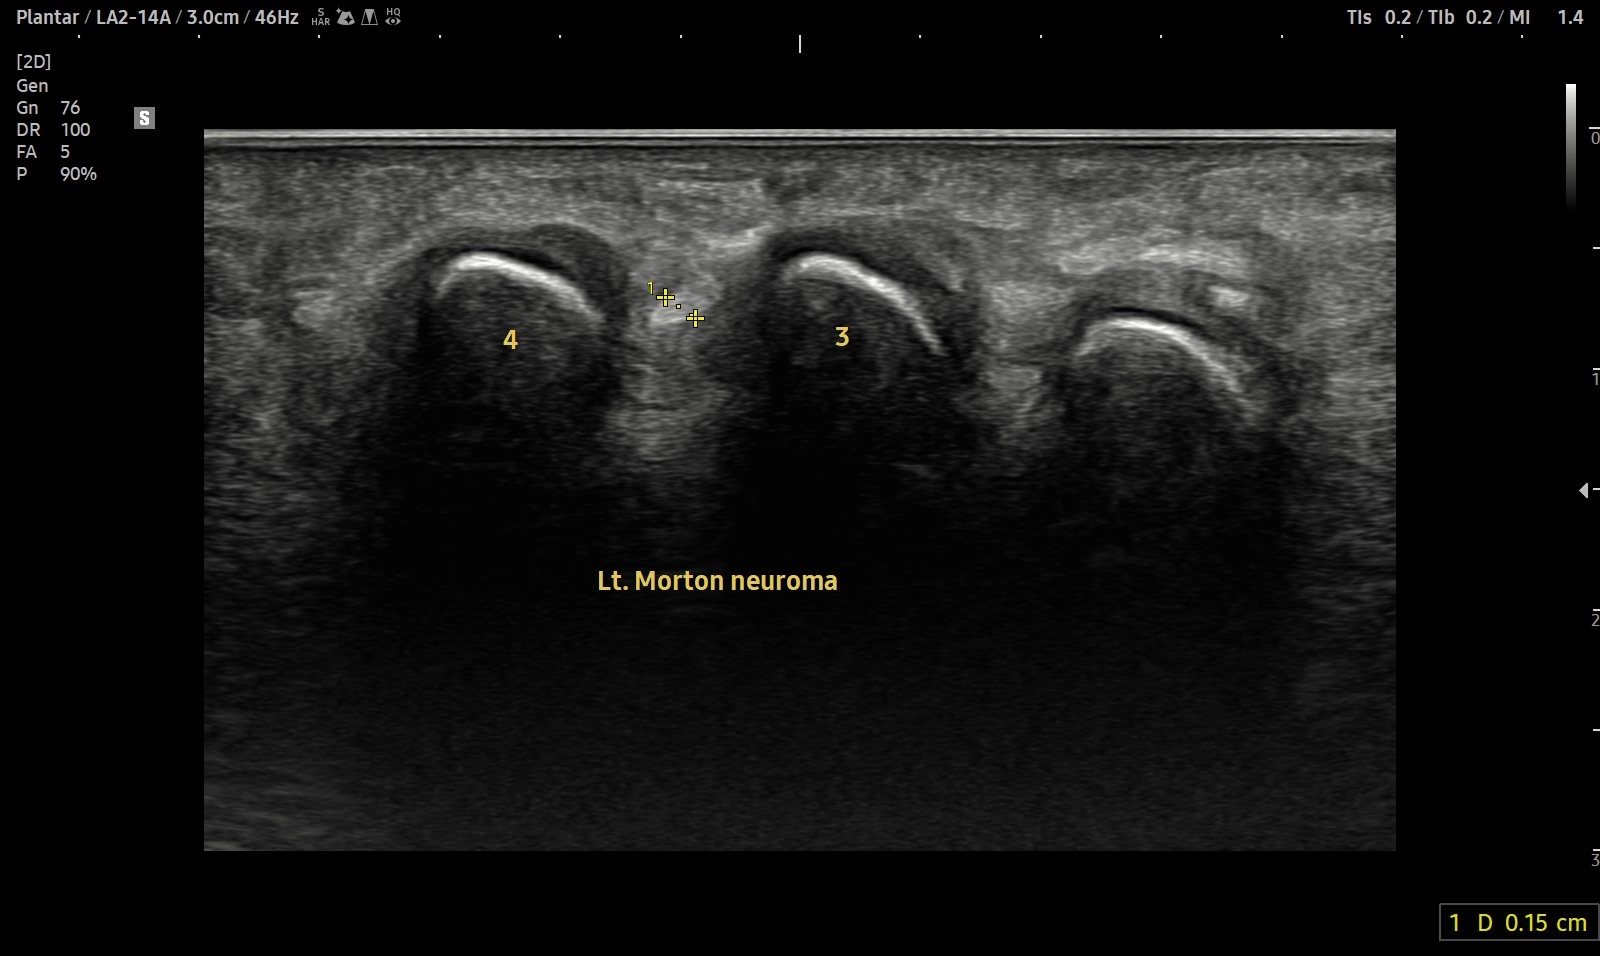

- 치료기간 : 25 . 4 . 1 ~ 25 . 5 26.

- 치료횟수 : 19 회

치료 전

치료 후